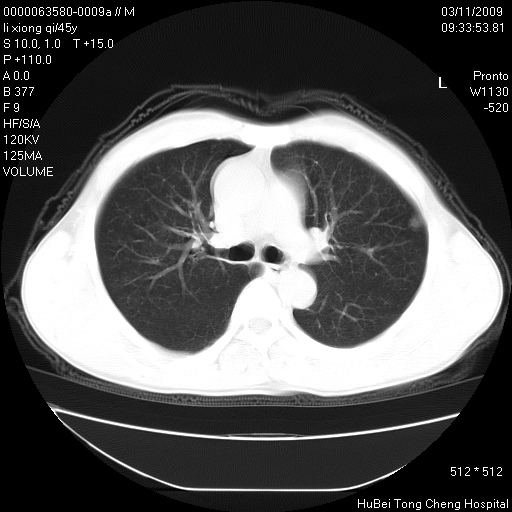

患者 男,45岁。胸痛,咳嗽伴痰中带血1月余。

临床诊断:肺结核?

胸部ct轴位平扫(层厚10mm,螺距1.5,重建间隔10mm),图像如下:

考虑肝癌肺转移